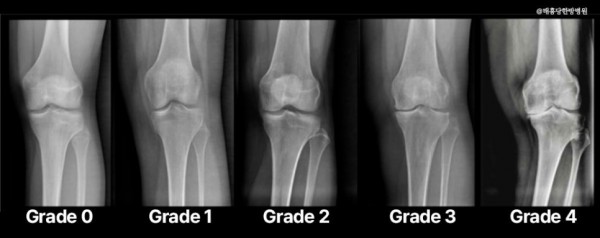

진행 정도를 정확히 평가하기 위해서는 엑스레이(X-ray)를 촬영합니다.

촬영 후 K-L(Kellgren-Lawrence) 분류법을 활용해 관절 간격의 좁아짐, 연골 마모, 그리고 골극(뼈 돌출)을

기준으로 관절염을 0단계부터 4단계까지 세분화하여 분석하게 돼요.

K-L(Kellgren-Lawrence) 분류법에 따라 증상을 다시 한번 짚어보겠습니다.

초기 단계(1~2단계)에서는 연골 손상이 경미하거나 관절 간격이 약간 좁아지는 정도로 증상이 거의 없을 수도 있지만,

중등도 이상(3단계)으로 진행되면 통증과 관절의 움직임 제한이 뚜렷하게 나타나게 돼요.

중증 단계(4단계)에서는 연골이 거의 사라져 뼈끼리 부딪히면서

심한 통증과 관절 변형이 동반될 수 있어요.